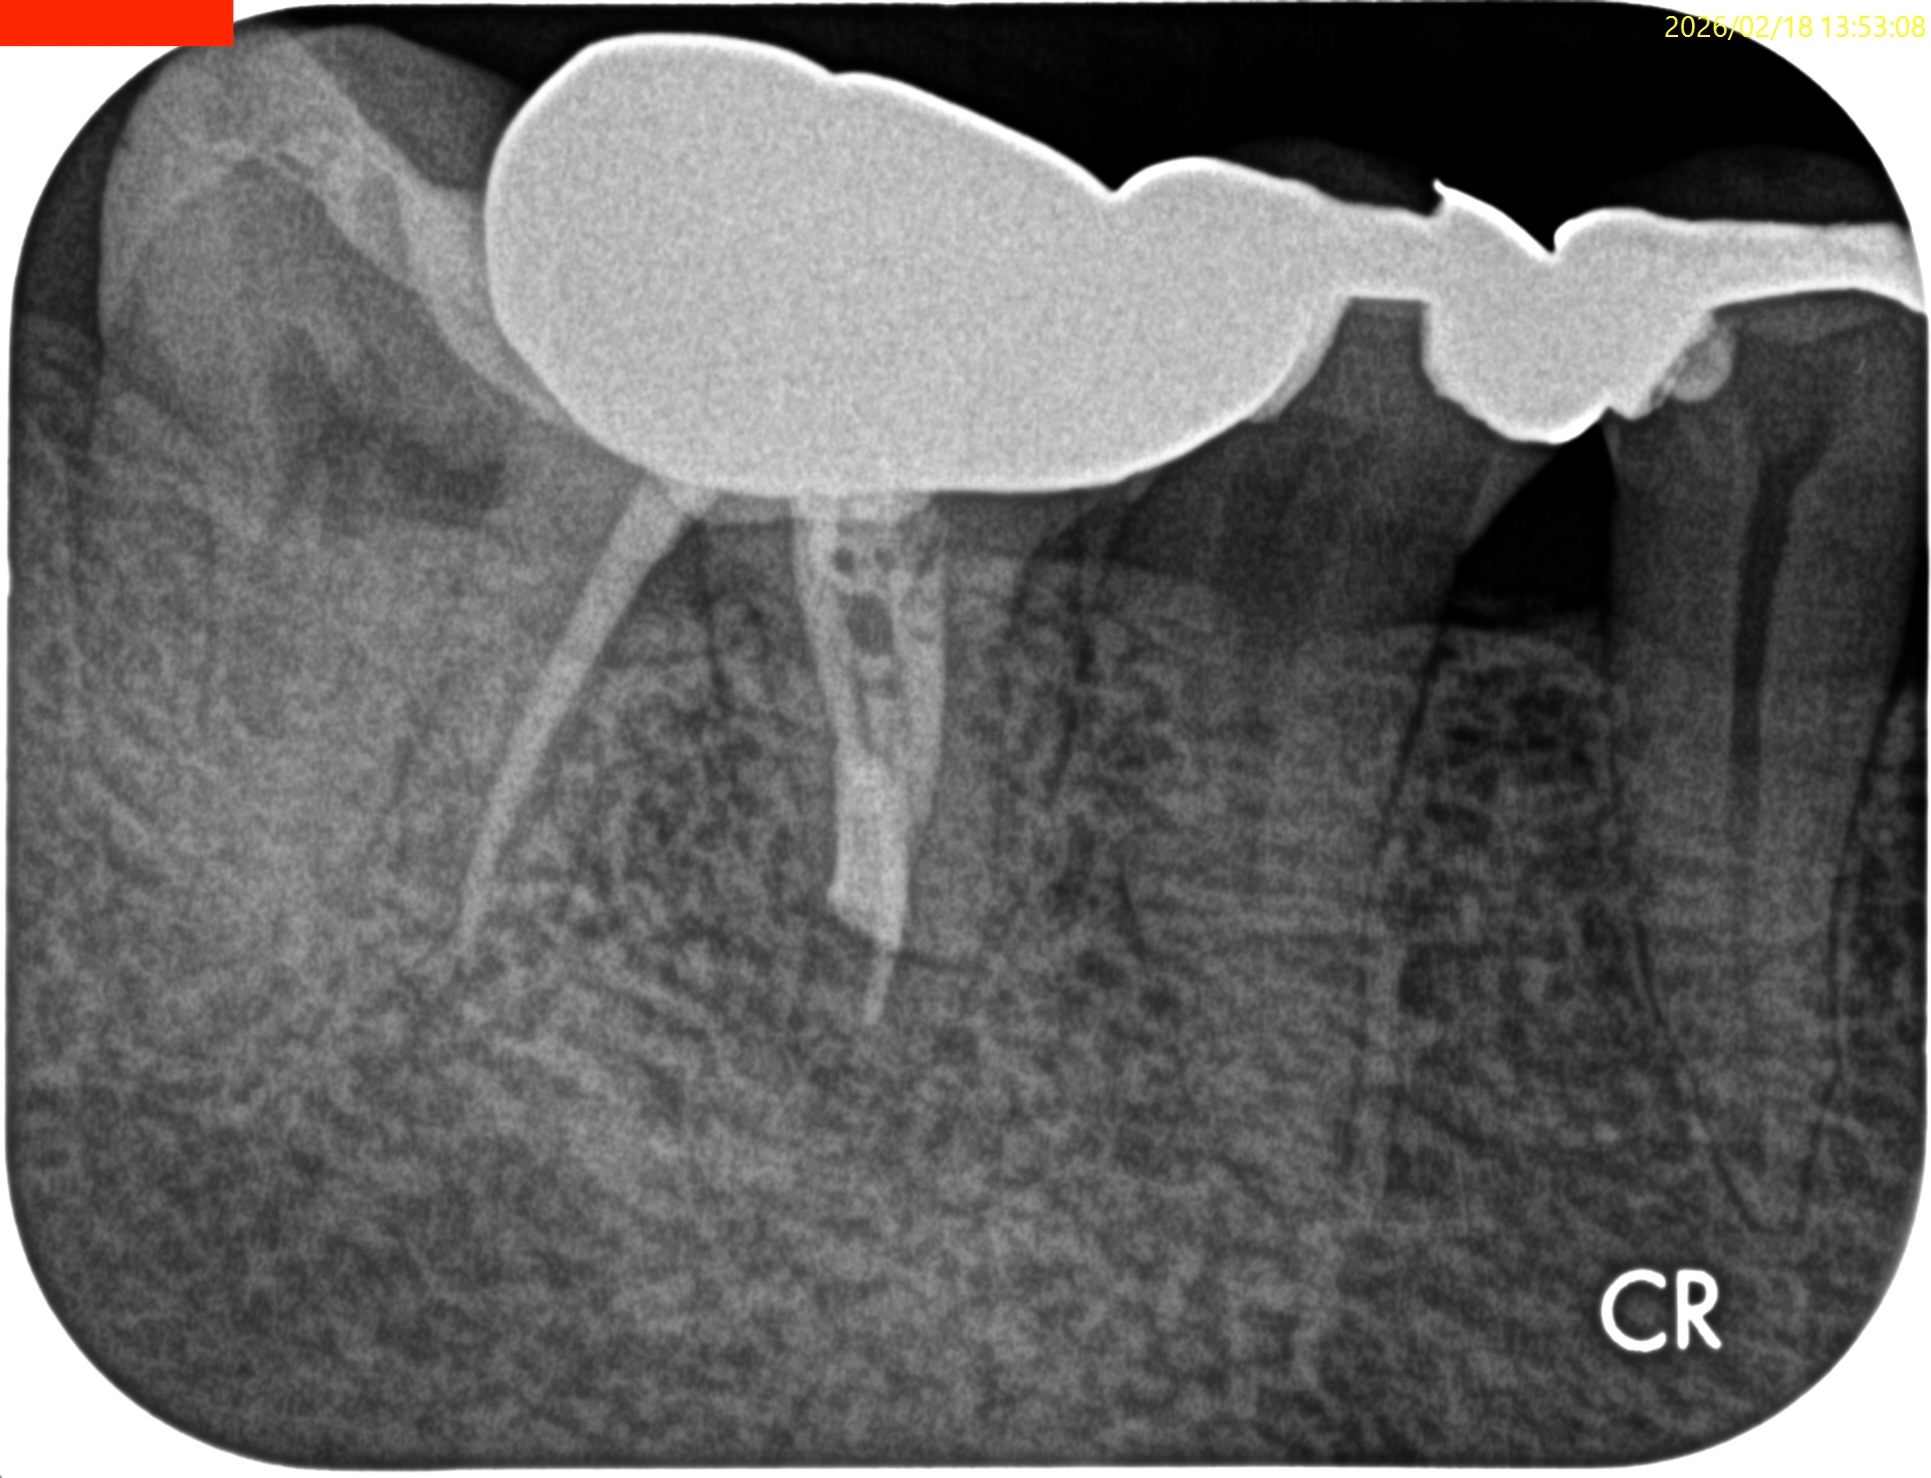

#30 M Apicoectomy 6M recall(2026.2.18)

大幅に問題が改善している。

初診時と比較した。

歯槽骨が劇的に再生している。

臨床症状もない。